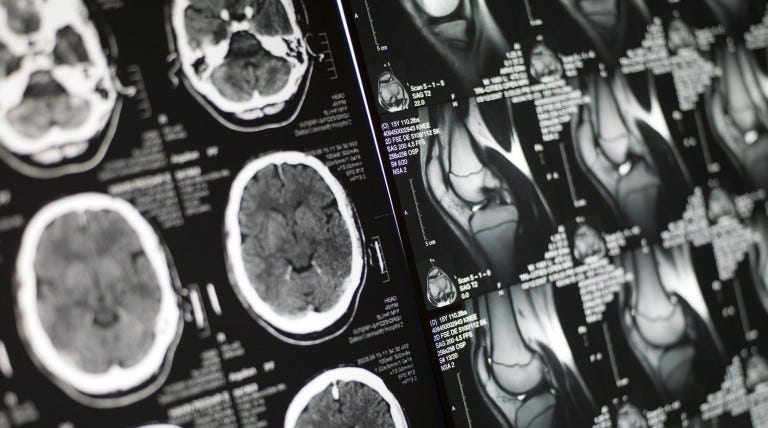

The radiologist probably requested the second MRI with contrast because he or she would like to report the best finding to your doctor who ordered the MRI. Ad Find out what magnetic resonance imaging MRI scans are used for right now. Routine MRI can also show that your treatment is working well for you. MRI scans have transformed how radiologists diagnose MS and are now the primary method doctors use to. Contrast is given for spine MRI scans to search for. MRI with contrast should be ordered when a more detailed view of organ structure and function is needed.

Some MRI exams require the use of a contrast injection. Why do I need a contrast injection. On the positive side you know that someone is looking out for you and taking your case. Adding contrast makes it possible for the radiologist to detect even the smallest tumor and provides information about the precise. Adding contrast makes it possible for the radiologist to detect even the smallest tumor and provides information about the precise. The primary difference is that for contrast MRIs a dye gadolinium-based is given to the patient intravenously prior to the scan.

Ad View a resource website for contrast agents injection systems MR accessories. Sometimes you need a second scan because the consultant radiologist wants to add some contrast to show up different pathologies. Therefore baseline images are needed before contrast to determine how much the brightness of the anatomy may have changed after contrast gets deposited in the tissues. MRI or CT scans with contrast are sometimes required when the doctor might want to concretely investigate an apparent abnormality. Depends on diagnosis. Efficient Workflow And Productivity For Routine Scanning.

Dr Google NEVER provides any good answers just scary ones. Why do I need a second MRI scan with contrast. Contrast agent is a substance that radiologists use to see body organs and tissues on the produced images more clearly aiding in post-scan diagnosis. Gadolinium contrast is used in about one in three MRI scans to improve the diagnostic accuracy of the scan. Ad Intuitive Products Redefining What MRI Can Be. Adding contrast makes it possible for the radiologist to detect even the smallest tumor and provides information about the precise.